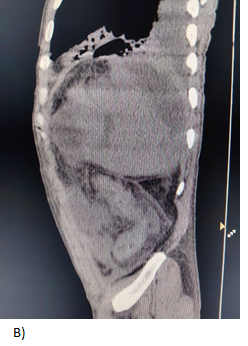

A 27-year-old male with a history of multiple hospitalizations and transfusions for dengue hemorrhagic fever, HIV (+) seven years ago with self-suspended treatment five months ago. He went to the emergency room due to abdominal pain in the epigastrium of three weeks' evolution accompanied by hyporexia, asthenia, and adynamia with hematochezia on one occasion, vomiting coffee grounds on one occasion with respiratory difficulty and dyspnea, denying fever or cough. Physical examination revealed moderate dehydration, pale integuments, tachypnea, and wheezing in the left hemithorax with wheezing in the right hemithorax, abdomen with signs of peritoneal irritation, vital signs: BP 100/60 mmHg, HR 154/min, Breaths 28/min, temp. 36.8 °C. Diagnosis of probable community-acquired pneumonia plus upper gastrointestinal bleeding, severe dehydration and HIV, hypovolemic shock, and septic shock are included. Laboratories: hemoglobin 5.5g/dL, leukocytosis (31000/103/L, absolute neutrophils 28 302/103L, lactic acidosis (PCO2 20.300 mmHg, PO2 73.40mmHg, HCO3 11.50mEq/L and lactate 12.60mmol/L). Tomography with data of honeycombing in both lungs to rule out PTB vs. PCP (Pulmonar tuberculosis vs. Probable Candida parapsilosis), left pleural effusion, bilateral atelectasis, and free peritoneal fluid with suspicion of probable gastric perforation. A CT scan is performed without specifying the origin of the septic shock (Figure 1 & 2). The patient is admitted to the operating room for exploratory laparotomy, purulent fluid (2500ml) is aspirated, a splenic abscess is identified on the diaphragmatic side and splenectomy is performed with the standard technique, admission to the Register Intensive Care Unit, later to the general surgery floor with an in-hospital stay of 9days, he is discharged with control by internal medicine, surgery and SAIH (Hospital Comprehensive Care Services).

Figure 1 Tomography showing a perisplenic collection of heterogeneous density with water and gas density, suggestive of splenic abscess and reactive perihepatic free fluid.